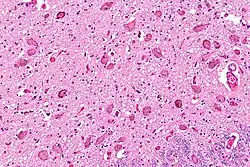

![]() Micrograph showing the locus coeruleus. HE-LFB stain. | |

The locus coeruleus (LC) is located in the posterior area of the rostral pons in the lateral floor of the fourth ventricle. It is composed of mostly medium-size neurons. Melanin granules inside the neurons of the LC contribute to its blue colour. Thus, it is also known as the nucleus pigmentosus pontis, meaning "heavily pigmented nucleus of the pons." The neuromelanin is formed by the polymerization of norepinephrine and is analogous to the black dopamine-based neuromelanin in the substantia nigra.

In adult humans (19-78) the locus coeruleus has 22,000 to 51,000 total pigmented neurons that range in size between 31,000 and 60,000 μm3.[4]